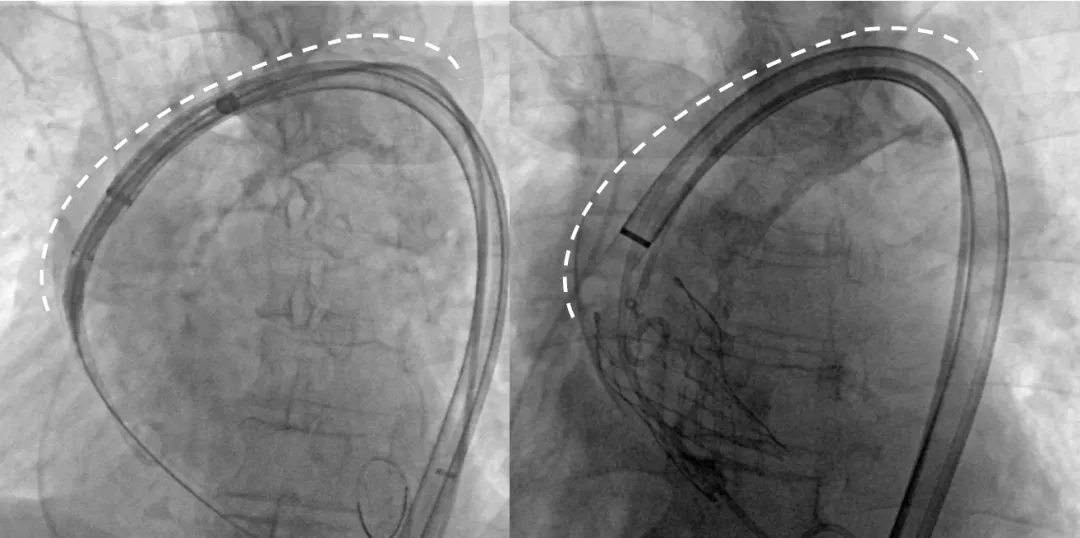

过弓示意图

Step 4.输送系统进入:过弓性能优异,悬空通过,整体过程未将鞘管顶起至弓顶部